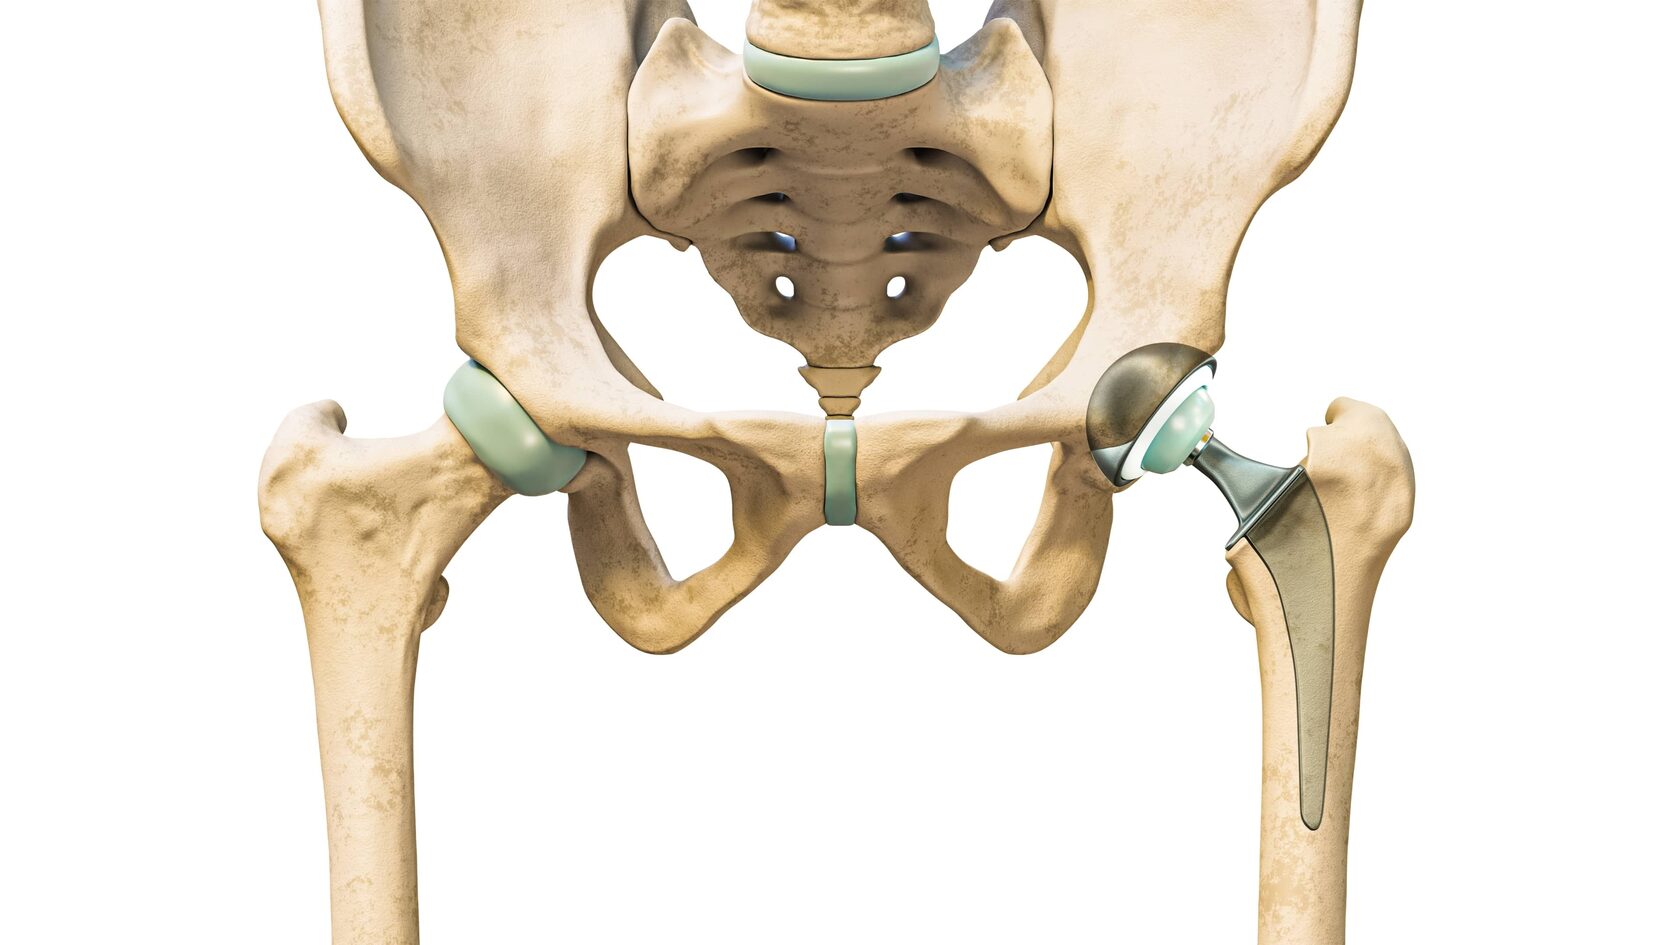

Иллюстрации и снимки, связанные с остеопенией шейки бедра